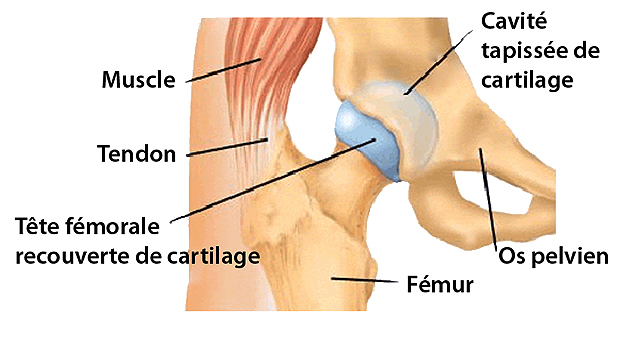

L'articulation de la hanche est formée d'une tête sphérique du côté du fémur et d'une cavité cotyloïdienne du côté du bassin.

La surface de la tête fémorale et de la cavité cotyloïdienne, où les os viennent en contact entre-eux, est recouverte par un tissu lisse appelé cartilage articulaire.

Le cartilage, lubrifié par une substance visqueuse appelée liquide synovial, empêche les os de frotter directement les uns contre les autres et de s'user.